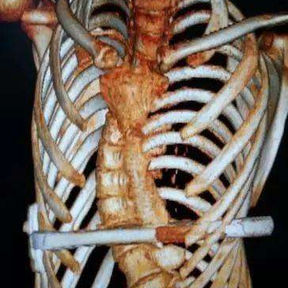

The patient is a 16-year-old male who has been diagnosed with pectus excavatum in childhood but experienced no discomfort in daily life. At the age of 15, he underwent Nuss procedure during which a bar was placed in his chest wall. However, the depression in his chest wall persisted after the surgery, and he even developed new severe deformities. As the deformities gradually worsened, the patient developed scoliosis, and his entire chest wall became completely distorted, eventually losing its basic shape. Later, the patient underwent another minimally invasive surgery for spontaneous pneumothorax, during which the surgeon ligated bilateral pulmonary bullae without treating the chest wall deformities. Ultimately, because of the severe deformities and breathing discomfort, the patient came to our hospital for treatment.

The patient was diagnosed with severe complex chest wall deformities accompanied by scoliosis. The heart was severely compressed and shifted to the left thoracic cavity.

We developed a personalized surgical plan for the patient. The operation first involved making incisions along the surgical scars on both sides of the chest wall to remove the bar inserted during the Nuss procedure. Then, a larger incision was made at the central scar on the anterior chest wall to fully expose the bone structure located at concave and convex areas of the chest wall. It was found that there were severe adhesions between the chest wall structure and the pericardium, with the heart being compressed into the left chest cavity.